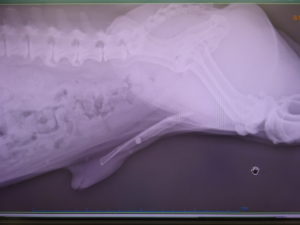

DSC043112021.02.04